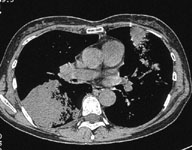

CaseKS08

Case A

X-ray CT